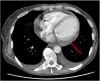

Case presentation: A 59-year-old female living in an intensive tertiary mental health facility was noted to have an incidental pericardial effusion during work-up for hyponatremia. Seven months later, she developed a new fever and was noted to have interval increase in the pericardial effusion size. This prompted further investigation which finally revealed that an ingested pen had perforated through the first part of the duodenum and caused an abscess in the left lobe of the liver. The pericardial effusion was presumed secondary to local inflammation. Upon discovery of the abscess, the patient underwent successful operative management including abscess drainage, foreign body extraction, and duodenal repair.